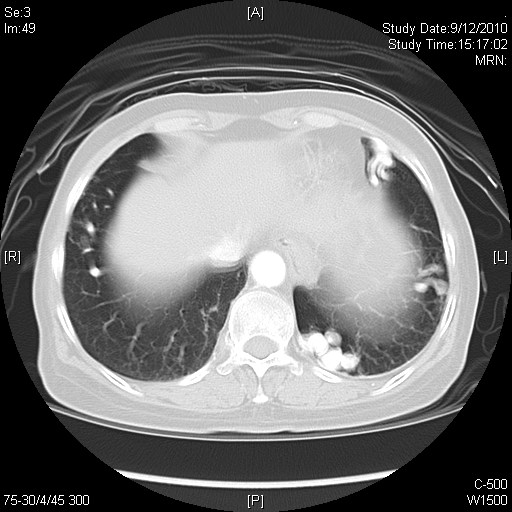

High resolution computer tomography (HRCT) scan of the thorax that time had no evidence of interstitial lung disease. Physical examination on admission revealed multiple telangiectasia over her forehead. Lung auscultations had no added sounds. Chest X-ray had no definite consolidative changes over lung fields. However, she was found to have persistent desaturation despite given high flow oxygen via non-rebreathing mask. White cell count was normal. Augmentin was empirically started. Arterial blood gas (ABG) showed type 1 respiratory failure with increased A-a gradient. She was eventually given Bi-level Positive Airway Pressure (BIPAP) support and intubated on day 2. Urgent contrast computer tomography scan of the thorax was performed, which incidentally found multiple PAVMs over bilateral lower zones of her lungs. There were no evidence of pulmonary embolism and no significant consolidative changes over both lungs. She was then transferred intensive care unit for further management and was successfully weaned from mechanial ventilation. Significant intra-pulmonary shunt was confirmed by contrast echocardiography. However, despite stabilization, she had persistent hypoxemia requiring oxygen supplement of 4L/min on discharge from acute medical ward. Detailed history confirmed that she had personal history of epistaxis since 25 year old. She was therefore diagnosed to have hereditary hemorrhagic telangiectasia by Cucao Criteria. Radionuclide scan by 99m Tc was arranged and shunt fraction was estimated to be 24.6% after calculation. Lung function test showed isolated decreased DLCO of 58% predicted after adjusted with alveolar volume.

Radiologically, contrast enhanced computer tomography scan is now widely used for diagnosing PAVM. With reconstruction techniques, it enables interventional radiologists to delineate the architecture of PAVM precisely. Conventional pulmonary angiography remains the gold standard but it is an invasive procedure.